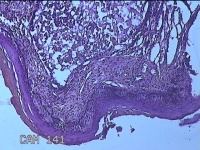

宫颈赘生物

性别

女

年龄

37岁

临床诊断

早期人工流产;宫颈炎性疾病

一般病史

宫颈有1赘生物。

标本名称

大体所见

灰白暗红色肿物1.3x0.8x0.2cm一个,表面糜烂。

息肉,那氏囊肿